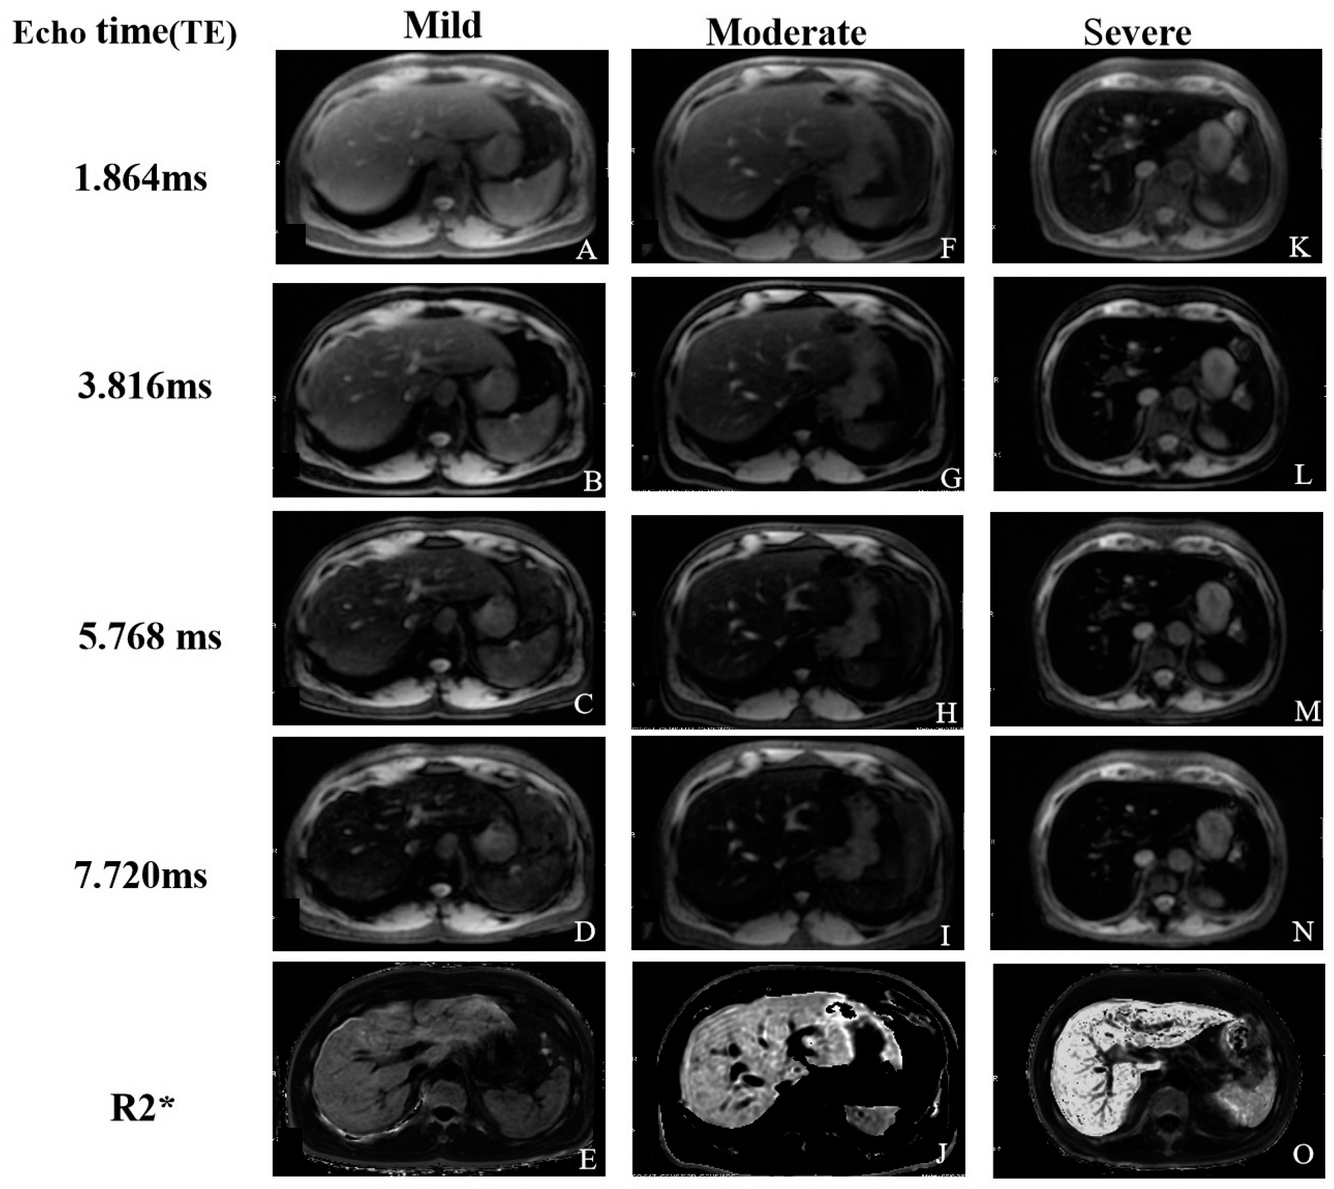

Perda do sinal do fígado em paciente com hemocromatose primária acentuada.

Graduação da sobrecarga férrica na RM.